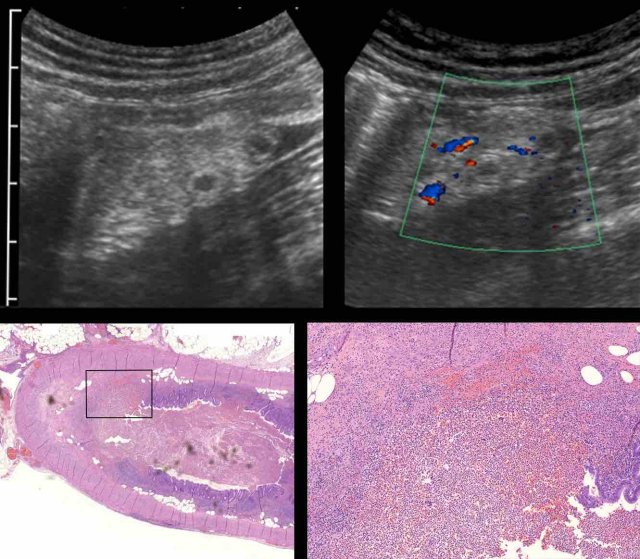

In this very lean patient with early acute appendicitis, US reveals dilatation of the distal appendix.

In plane A, Doppler US shows strong hypervascularization of the wall, however in plane B no vessels are visible in the appendix wall due to high intraluminal pressure.

Note the dilated, non-compressible, round appendix in B, bulging into the abdominal wall during compression (arrowheads), with only vascularization in the fatty meso-appendix.

As shown earlier, the vascularization of the appendix wall is initially decreased due to high intraluminal pressure.

However, this high pressure will drop again rapidly since the diseased appendix mucosa is not able to maintain its normal fluid production anymore.

As a result, in combination with the massive inflammatory response , strong reactive hypervascularization will occur rapidly: first in the surrounding fatty tissue and, soon after, also within the appendix wall.

Since this is the point in time, where patients usually seek medical help, this is the most familiar US image of the inflamed appendix.